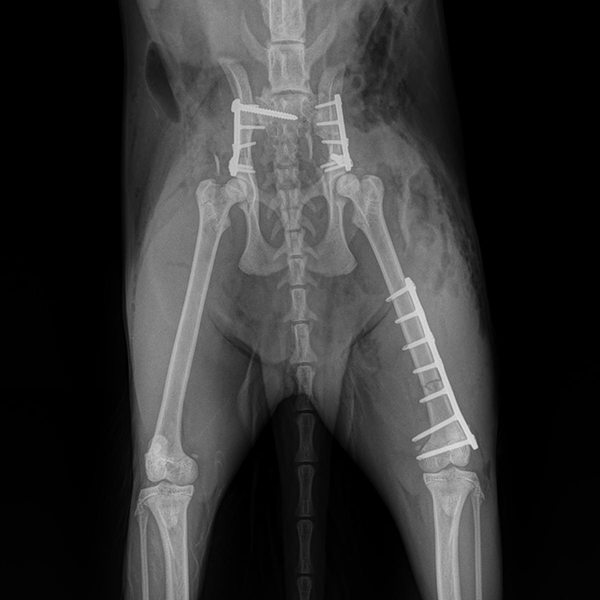

Case Overview In November 2025, Skeeter, a 14-week-old Doodle puppy weighing ...